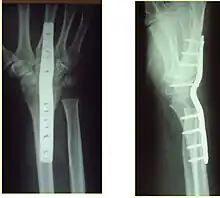

Surgery is generally indicated for displaced or unstable fractures.[18] The techniques of surgical management include open reduction internal fixation (ORIF), external fixation, percutaneous pinning, or some combination of the above. The choice of operative treatment is often determined by the type of fracture, which can be categorized broadly into three groups: partial articular fractures, displaced articular fractures, and metaphyseal unstable extra- or minimal articular fractures.[5]

Significant advances have been made in ORIF treatments. Two newer treatments are fragment-specific fixation and fixed-angle volar plating. These attempt fixation rigid enough to allow almost immediate mobility, in an effort to minimize stiffness and improve ultimate function; no improved final outcome from early mobilization (prior to 6 weeks after surgical fixation) has been shown. Although restoration of radiocarpal alignment is thought to be of obvious importance, the exact amount of angulation, shortening, intra-articular gap/step which impact final function are not exactly known. The alignment of the DRUJ is also important, as this can be a source of a pain and loss of rotation after final healing and maximum recovery.

Little joint involvement

These fractures are the most common of the three groups mentioned above that require surgical management.[5] A minimal articular fracture involves the joint, but does not require reduction of the joint. Manipulative reduction and immobilization were thought to be appropriate for metaphyseal unstable fractures. However, several studies suggest this approach is largely ineffective in patients with high functional demand, and in this case, more stable fixation techniques should be used.[20][21][22]

Surgical options have been shown to be successful in patients with unstable extra-articular or minimal articular distal radius fractures. These options include percutaneous pinning, external fixation, and ORIF using plating. Patients with low functional demand of their wrists can be treated successfully with nonsurgical management; however, in more active and fit patients with fractures that are reducible by closed means, nonbridging external fixation is preferred, as it has less serious complications when compared to other surgical options.[5] The most common complication associated with nonbridging external fixation is pin tract infection, which can be managed with antibiotics and frequent dressing changes, and rarely results in reoperation.[5] The external fixator is placed for 5 to 6 weeks and can be removed in an outpatient setting.[5]

If the fractures are unlikely to be reduced by closed means, open reduction with internal plate fixation is preferred.[5] Although major complications (i.e. tendon injury, fracture collapse, or malunion) result in higher reoperation rates (36.5%) compared to external fixation (6%), ORIF is preferred, as this provides better stability and restoration of the volar tilt.[5][23] Following the operation, a removable splint is placed for 2 weeks, during which time patients should mobilize the wrist as tolerated.[5]